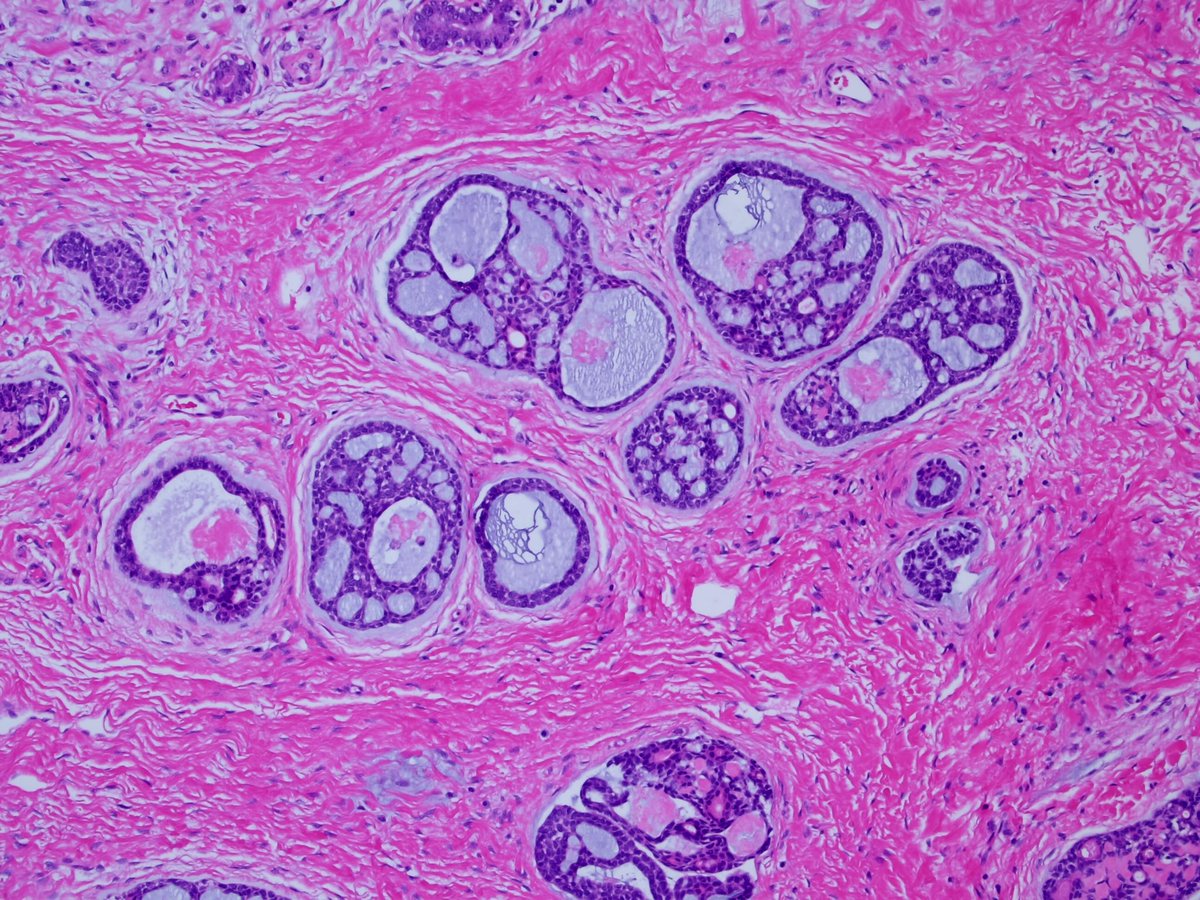

1. #Breastpath, with an #ENTpath flavor A case I had which pairs well with this sweet diagram by@TheKarenPinto (linked below) 40 year old woma